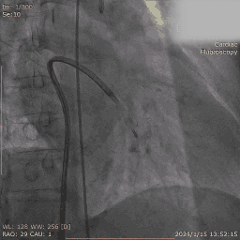

Step 5. 主动脉瓣定位及释放

Step 6. 复查造影示瓣膜支架膨胀良好,少量瓣周漏